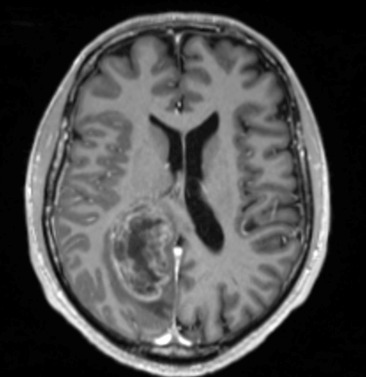

M. V., 41 ans, droitier, est adressé aux urgences où vous exercez, pour un épisode de mouvements cloniques hémicorporels gauches durant près de 10 minutes, sans perte de connaissance, avec un teint bleuté.

Son épouse ne rapporte pas d’antécédent particulier, il ne présente pas de troubles cognitifs. Elle signale tout de même que cela fait plusieurs fois qu’elle touche le bras gauche de son mari sans qu’il ne s’en aperçoive. De plus, il a récemment endommagé le rétroviseur côté conducteur de leur véhicule lors d’une manœuvre de stationnement. Il ne prend pas de traitement. Il ne fume pas et ne boit qu’occasionnellement. Il est sportif, en bon état général par ailleurs. Il se plaint parfois de céphalées avec sensation d’étaux, prédominantes à droite, qui résistaient aux antalgiques simples (paracétamol) depuis plus de 3 semaines.

Cliniquement, vous constatez une hémiparésie brachio-faciale gauche, apparue juste après l’épisode de mouvements anormaux et qui semble être en train de régresser selon les pompiers.